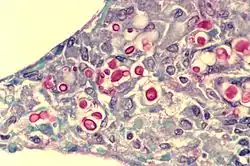

| Yeast state of Cryptococcus neoformans | |

Cryptococcus neoformans typically grows as a yeast (unicellular) and replicates by budding. It makes hyphae during mating, and eventually creates basidiospores at the end of the hyphae before producing spores. Under host-relevant conditions, including low glucose, serum, 5% carbon dioxide, and low iron, among others, the cells produce a characteristic polysaccharide capsule.[8] The recognition of C. neoformans in Gram-stained smears of purulent exudates may be hampered by the presence of the large gelatinous capsule which apparently prevents definitive staining of the yeast-like cells. In such stained preparations, it may appear either as round cells with Gram-positive granular inclusions impressed upon a pale lavender cytoplasmic background or as Gram-negative lipoid bodies.[9] When grown as a yeast, C. neoformans has a prominent capsule composed mostly of polysaccharides. Under the microscope, the India ink stain is used for easy visualization of the capsule in cerebral spinal fluid.[10] The particles of ink pigment do not enter the capsule that surrounds the spherical yeast cell, resulting in a zone of clearance or "halo" around the cells. This allows for quick and easy identification of C. neoformans. Unusual morphological forms are rarely seen.[11] For identification in tissue, mucicarmine stain provides specific staining of polysaccharide cell wall in C. neoformans. Cryptococcal antigen from cerebrospinal fluid is thought to be the best test for diagnosis of cryptococcal meningitis in terms of sensitivity, though it might be unreliable in HIV-positive patients.[12]